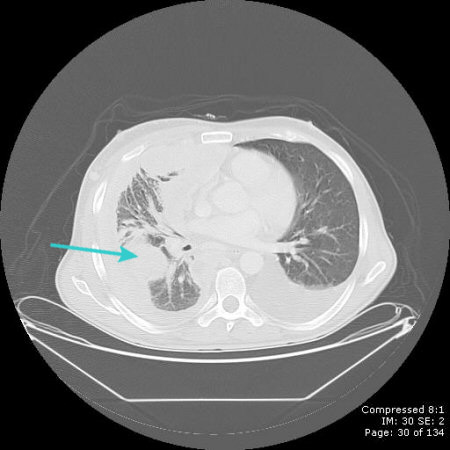

[Figure caption and citation for the preceding image starts]: CT scan showing large right pleural effusionFrom the collection of Dr Nicholas Maskell; used with permission [Citation ends].